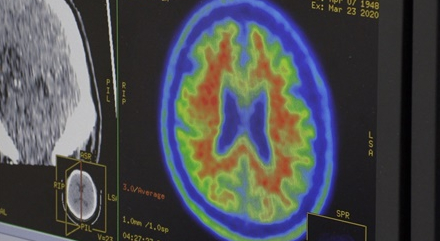

백세 시대, 80세 이상 노인 인구 중 4명 중 1명이 치매이고 65세 이상 노인들이 가장 두려워하는 질병이 치매다. 알츠하이머성 치매는 무증상 기간이 15여 년, 경도인지장애가 나타난 후 5년, 치매 진단을 받은 후 평균 8년 생존하기 때문에 무증상단계에서의 발견과 예방이 중요한 질병이 아닐 수 없다. 4년 전 치매 진단을 받은 최정신 씨와 파킨슨병을 앓고 있는 아내 양정자 씨 부부는 자식들에게 의존하지 않고 일상생활을 하고 있다. 가까이 사는 딸은 늘 불안한 마음에 매일 친정 부모의 안위를 챙겨야 하는 현실. 무기력증에 빠진 아버지를 보면서 늦게 진단을 받은 것에 내내 후회스럽다. 이처럼 막연히 불안해할 뿐 대부분 치매가 진행된 후에 진단을 받는다.

이에 7년 전부터 조선대학교 의생명과학과 이건호 교수는 치매국책사업단을 꾸리고 광주치매예방센터를 운영하면서 조선대광주치매코호트 연구를 해오고 있다. 그들은 코호트 연구를 통해 정상인을 대상으로 MRI 뇌 영상을 분석하여 한국인 표준 뇌지도를 만들었다. 이는 정상인의 뇌지도와 비교해 알츠하이머병 초기의 뇌 손상 상태를 확인할 수 있는 기술이다. 또한, 혈액검체은행에 쌓인 1만 3천여 명의 유전체 데이터는 이를 토대로 추적 검사를 통해 치매 진행 과정을 밝힐 수 있는 단초가 될 것으로 기대되고 있다. 중앙대 신경과 윤영철 교수와 치매 혈액 진단법을 개발해온 한 기업이 피 한 방울로 치매 위험도를 측정하는 기술을 발표해서 상용화를 앞두고 있다. 아밀로이드 물질의 뭉치는 성질을 이용한 검사법으로 아밀로이드의 축적도를 가늠할 수 있다는 원리다.